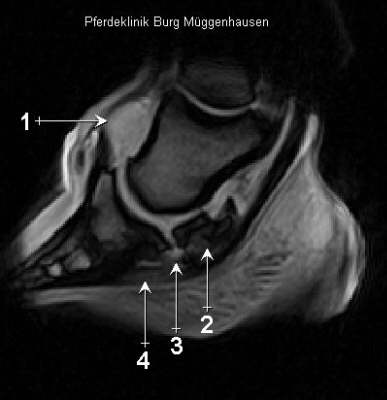

MRT Längsschnitt

1 Das Hufgelenk ist hochgradig gefüllt.  2 Der ansonsten in diesem Bereich als feine helle Linie dargestellte Hufrollenschleimbeutel ist nicht mehr erkennbar. 3 Im unteren Strahlbeinband  stellt sich die Schädigung als eine signalreiche Struktur (Flüssigkeit) dar. 4 Die tiefe Beugesehne ist hier diffus mit Flüssigkeit durchsetzt, was man als leichte Grauschattierung erkennt.